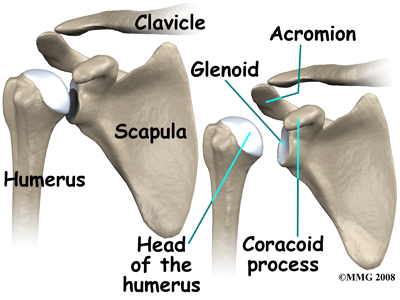

The shoulder is made up of three bones: the scapula (shoulder blade), the humerus (upper arm bone), and the clavicle (collarbone).

The shoulder is made up of three bones: the scapula (shoulder blade), the humerus (upper arm bone), and the clavicle (collarbone).

Tendons attach muscles to bones. Muscles move the bones by pulling on the tendon that they attach to. The rotator cuff muscles help raise and rotate the arm. As the arm is raised, the rotator cuff also keeps the humerus tightly in the socket. The socket of the shoulder is part of the scapula bone and is called the glenoid fossa. The glenoid fossa is very shallow and flat so without the rotator cuff muscles the top part of the humerus (the head) would slide out of the centre of the fossa.

The part of the scapula that connects to the lateral shoulder is called the acromion. A bursa is located between the acromion and the rotator cuff tendons. A bursa is a lubricated sac of tissue that cuts down on the friction between two moving parts. Bursae are located all over the body where tissues must rub against each other. In this case, the bursa protects the acromion and the rotator cuff from grinding directly against each other.

The humeral head of the shoulder is the ball portion of the shoulder joint. The humeral head has several blood vessels, which enter at the base of the articular cartilage. Articular cartilage is the smooth, white material that covers the ends of bones in most joints. Articular cartilage provides a slick, rubbery surface that allows the bones to glide over each other as they move. Cartilage also functions as a shock absorber in the joint.

A watertight sac called the joint capsule surrounds the shoulder joint. The joint capsule holds fluids that lubricate the joint. The walls of the joint capsule are made up of ligaments. Ligaments are connective tissues that attach bones to bones. The joint capsule has a considerable amount of slack (loose tissue), so that the shoulder is unrestricted as it moves through its large range of motion.